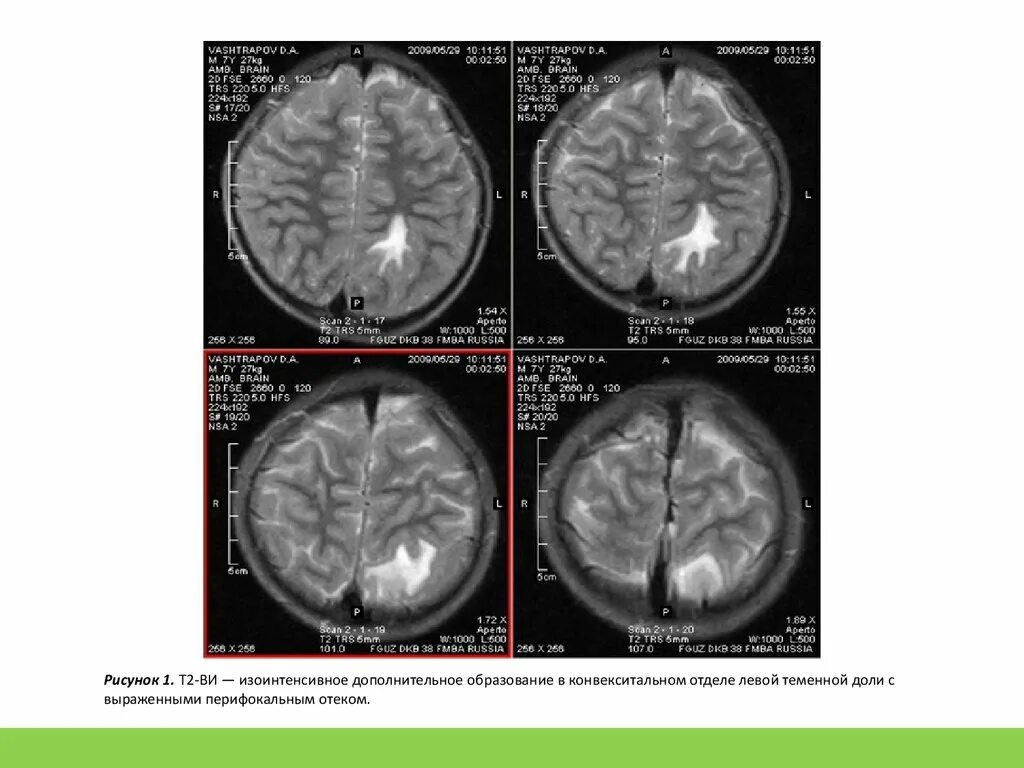

Перифокальный отек образования